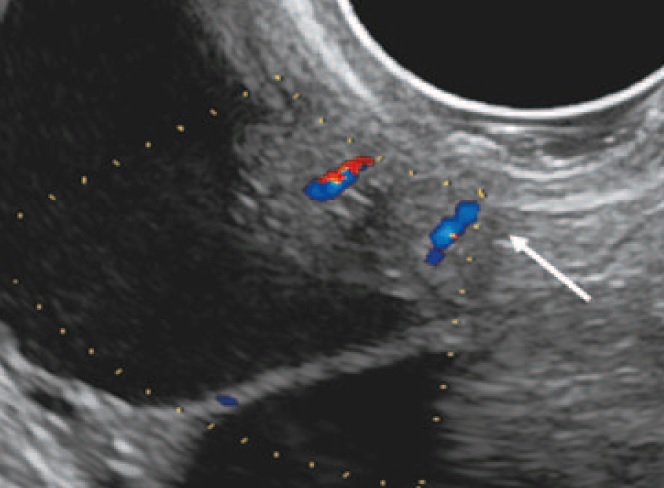

Во 2-й группе – 15 (9,8% наблюдений) – по данным УЗИ объемных образований в яичнике обнаружено не было, тем не менее больные были повторно оперированы. В одном наблюдении при неизмененной структуре неувеличенного яичника по его контуру визуализировались плотные структуры, идентичные псаммомным тельцам, что послужило основанием заподозрить опухоль (рис. 1).

Рис. 1. Ультразвуковая томограмма яичника. На изображении по контуру неувеличенного яичника определяются точечные гиперэхогенные структуры, соответствующие псаммомным тельцам.

Fig. 1. Ultrasound image of the ovary. The ultrasound image showing the hyperechoic structures corresponding to the psammoma bodies along the outline of the normal sized ovary.